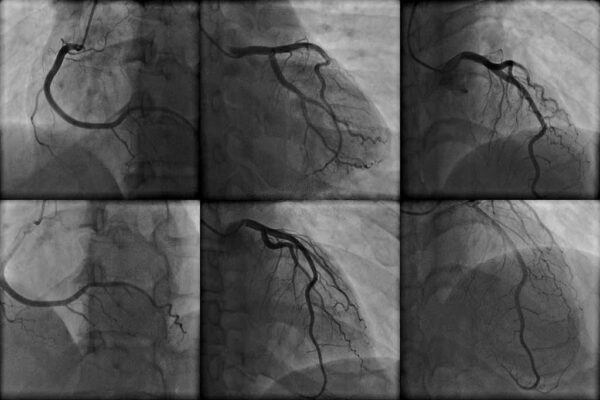

أثناء عملية قسطرة القلب سوف يتم حقن صبغة ملونة الى داخل الشرايين من خلال قسطرة (أنبوبة بلاستيكية رقيقة) بينما يقوم طبيب القلب المعالج بمتابعة تدفق الدم عبر القلب على شاشة جهاز أشعة إكس.

سوف يقوم طبيب القلب المعالج بتنظيف وتخدير منطقة أصل الفخذ أو الذراع بواسطة البنج. قد يكون هناك إحساس ببعض الضغط الخفيف نتيجة إدخال ما يشبه الجيب في أحد الشرايين. سوف يتم توجيه القسطرة (أنبوبة رقيقة) بلطف الى أعلى وحتى الوصول الى أحد شرايين القلب. سوف يقوم طبيب القلب المعالج بمراقبة والاشراف على العملية بشكل كامل من خلال شاشة عرض أمامه.

النتائج سوف تظهر إن كان تدفق الدم الى ومن القلب يسير بشكل طبيعي أو إن كان هناك أي انسدادات. النتائج الغير طبيعية تعني وجود انسداد في شريان أو أكثر. في حالة وجود انسداد في أحد الشرايين قد يقوم طبيب القلب المعالج باللجوء لقسطرة علاجية أثناء عملية القسطرة التشخيصية ومن الممكن أن يقوم بتثبيت دعامة شريانية لتحسين تدفق الدم بشكل فوري.